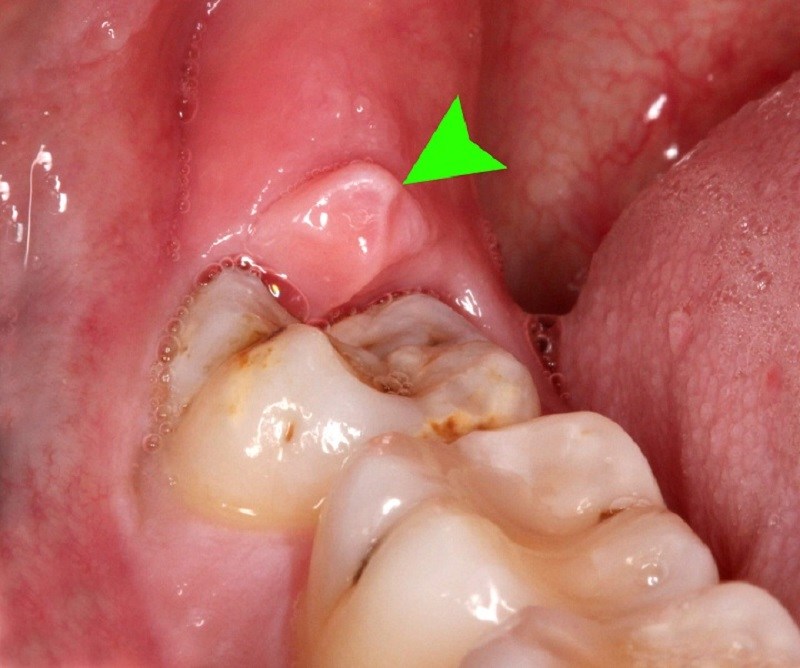

- Sưng lợi: ở độ tuổi trưởng thành, phần lợi đã chắc lại và xương hàm không còn phát triển nữa nên khi mọc răng khôn, lợi sẽ bị dãn ra và phồng lên.

Hình ảnh lợi bị sưng khi mọc răng khôn